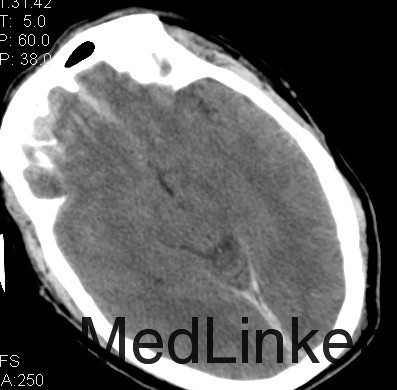

主诉:头部外伤7小时 病史:患者于7小时余前不慎从2米高处坠落,头部着地,并昏迷,左侧外耳道出血,无呕吐,无肢体抽搐,无明显头晕及头痛,无胸闷心悸,呼120入我院急诊诊治,行头颅CT提示有:头部螺旋CT平扫:1、蛛网膜下腔出血;大脑镰硬膜下出血;双侧额叶脑挫伤;脑肿胀。2、左侧枕骨骨折;左侧顶枕部头皮下血肿。3、双侧筛窦炎症。入急诊后患者神志转清,在急诊给予止血、脱水等治疗,4小时后复查头颅CT提示血肿增大及挫裂伤较前明显加重,为进一步治疗,收入我科。患者起病前,精神食欲可,二便可,体重无明显变化。

查体:神志昏睡,间断烦躁,刺激可睁眼,无对答,查体不合作,双侧瞳孔等大等圆,直径3mm,对光反应尚可,枕部可见隐约血肿,约1*1cm,左耳见血性液体流出。深浅感觉查体及腱反射查体不合作,双侧病理征未引出。格拉斯哥评分9分。 4:辅助检查:头部螺旋CT平扫(套:1、蛛网膜下腔出血;大脑镰硬膜下出血;双侧额叶脑挫伤;脑肿胀。2、左侧枕骨骨折;左侧顶枕部头皮下血肿。3、双侧筛窦炎症。颈椎螺旋CT平扫+三维:寰椎与枢椎齿状突之间高密度影,考虑撕脱骨折与钙化灶鉴别,建议复查或MRI进一步检查。

诊断:1、双侧额挫裂伤; 2、大脑镰、右侧额颞硬膜下出血;3、右额颞脑出血; 4、左枕骨骨折; 5、中枢神经系统感染 主要经过:入院后完善术前相关检查,行右侧额颞脑挫裂伤清除+去骨瓣减压+颅内压探头置入术;后行左侧额叶血肿清除+额颞顶去骨瓣减压术,术后予以抗感染、营养神经、改善循环、化痰、护胃、抗癫痫及营养支持治疗。 术后复查CT:双侧额颞顶骨局部缺如;左侧枕骨不连。 双侧额颞顶部皮下软组织稍肿胀。双侧额叶软化灶;右侧额颞部硬膜下及大脑纵裂池积液;右侧额颞部少量积气